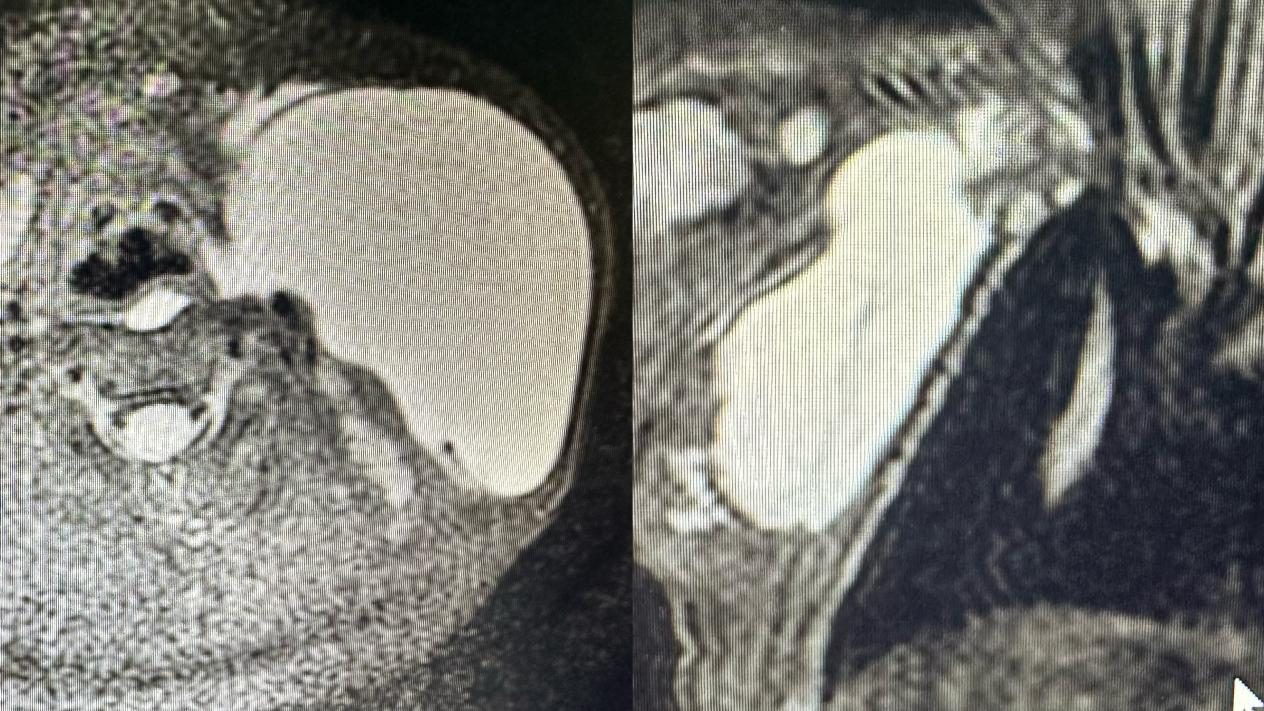

【辅助检查】1、超声检查提示无回声区,有分隔,呈囊状改变,CDFI:无血流信号,2、磁共振检查提示长T1长T2信号,囊状改变,压脂序列呈高信号,增强无明显强化。目的:1、超声检查用于明确诊断,2,磁共振检查用于了解淋巴管畸形病灶范围、侵及周围组织情况以及是否包绕重要器官如血管神经以及气管等。

儿童淋巴管畸形磁共振检查